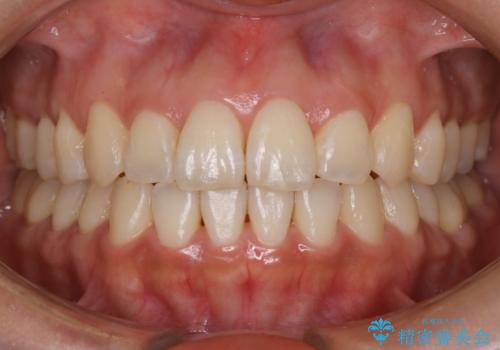

【非抜歯】ガタつきと歯軸を正して長持ちする歯へ

- 歯のガタつきと噛み合わせの改善を主訴に来院されました。

非抜歯で、少量の奥歯の移動と歯列の拡大・IPRを駆使して主訴を改善するための治療計画を立案しました。